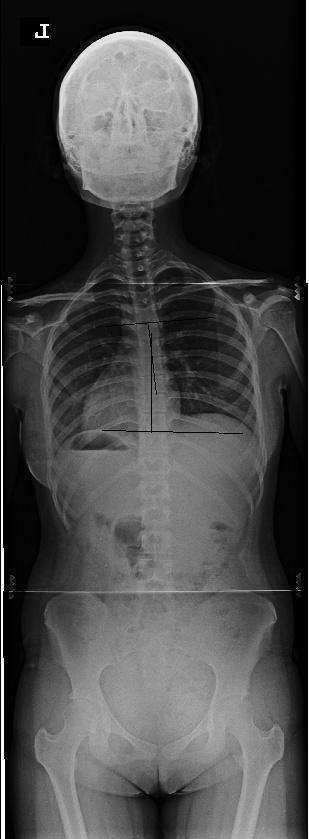

척추 측만증 치료 사례 2

분석 : 치료 전 13도의 측만에서 치료 후 7도의 측만으로 5도 정도의 호전을 보였습니다. .

치료 : 주 1회, 3개월간 치료 하였으며 호전 상태는 매우 양호합니다. 치료과정에서의 측만각도 호전을 보이고 있으나 현재 완전한 회복을 이룬 것은 아니므로 지속적인 치료가 필요합니다. 턱관절이 좋이 않아 학업에 지장이 많았으나 현재 턱관절도 좋아진 상태이며 추나요법과 매선요법을 겸하여 치료 하였습니다. 현재 과전만 치료 중 입니다.